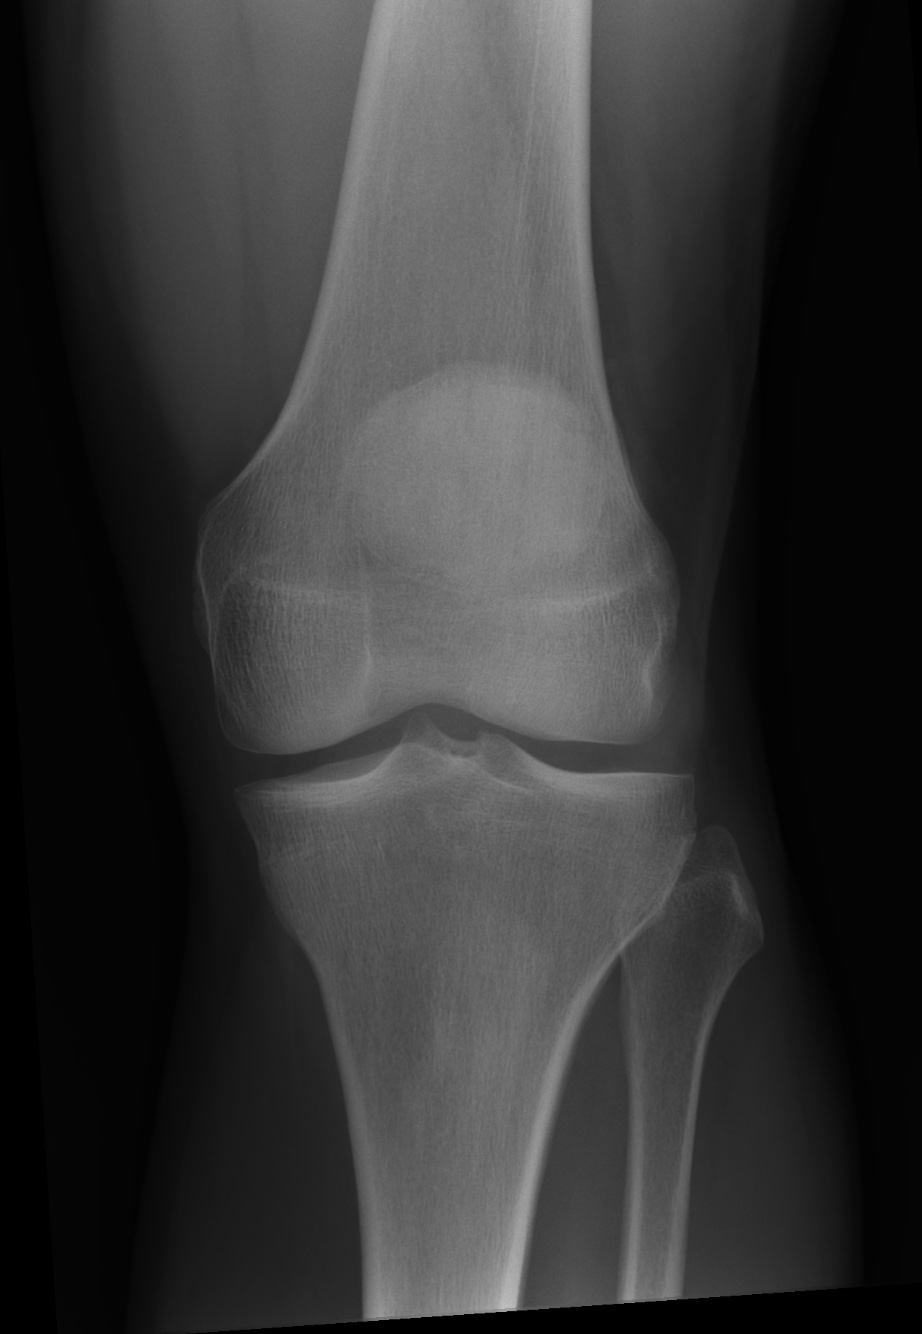

Die Beurteilung zur Knieendoprothese bei Gonarthrose basiert auf der aktuellen S2k-Leitlinie der DGOU. Diese Leitlinie wurde erstmals im April 2021 veröffentlicht und zuletzt am 13.03.2023 umfassend überarbeitet. Sie vereint sowohl evidenzbasierte Erkenntnisse als auch breite Expertenkonsens.